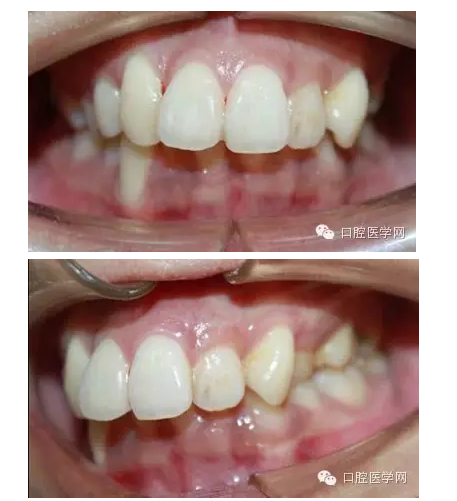

這是一位我同事接診的一位患者,成年女性,安氏II類,高角,下頜后縮,重度深覆合,上下中線右偏,原本做過一次矯正,4個4已經(jīng)拔除。

這個患者,II類高角,下頜后縮,所以我們不能抬高磨牙,另外兩個上頜中切牙牙根短小,也不能大幅壓入。